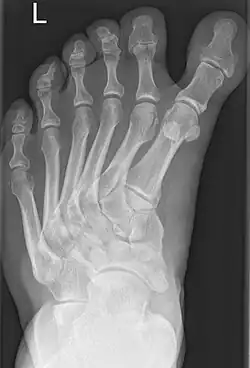

| Polydactyly-associated polymetatarsia. | |

Polymetatarsia is a rare congenital malformation which is characterized by the presence of 6 or more metatarsal bones in the same foot. It is most commonly seen alongside polydactyly,[1] and it often appears between the fourth and fifth metatarsals or beside the fifth metatarsal.